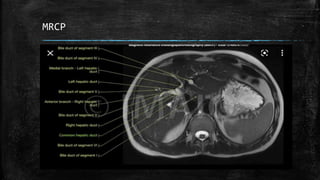

▪ Imaging (Diagnostic): Abdominal X-ray, CT scan/ultrasound,

ERCP(which can also be therapeutic)/MRCP

MRCP